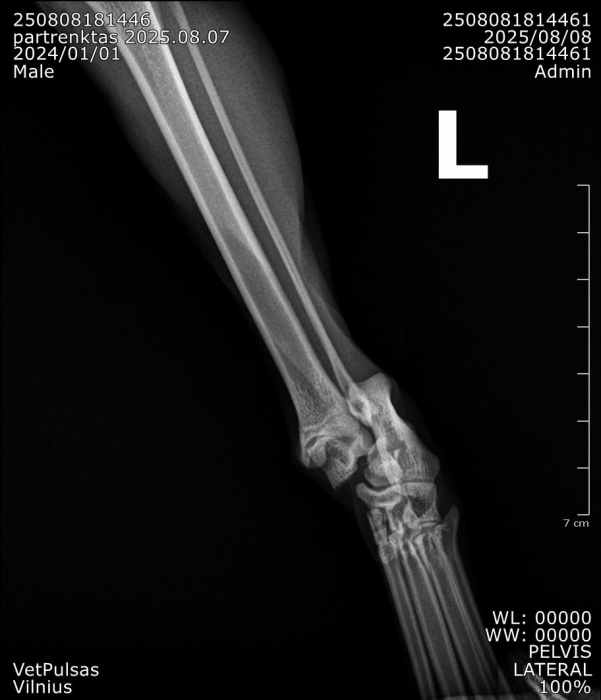

Į veterinarijos kliniką žmonės atvežė automobilio nutrenktą katinuką. Atlikus rentgeną paaiškėjo, kad abi užpakalinės kojos per sąnarius suknežintos į skeveldras. Vienos kojos raiščiai nutraukti. Apžiūrėjusi nuotraukas ir įvertinusi skeveldrinius lūžius chirurgė informavo kad operacija bus itin sudėtinga ir brangi. Vienu metu ji galėtų atlikti tik vienos kojytės operaciją, o po savaitės ar daugiau žiūrint kokia gyvūno būklė galės operuoti antrą. Visa tą laiką katinukas bus klinikos stacionare.

Chirurgė perspėjo kad operacija, gydymas ir pooperacine slauga klinikoje kainuos tikrai pakankamai daug nes užtruks mėnesį ar net daugiau laiko.